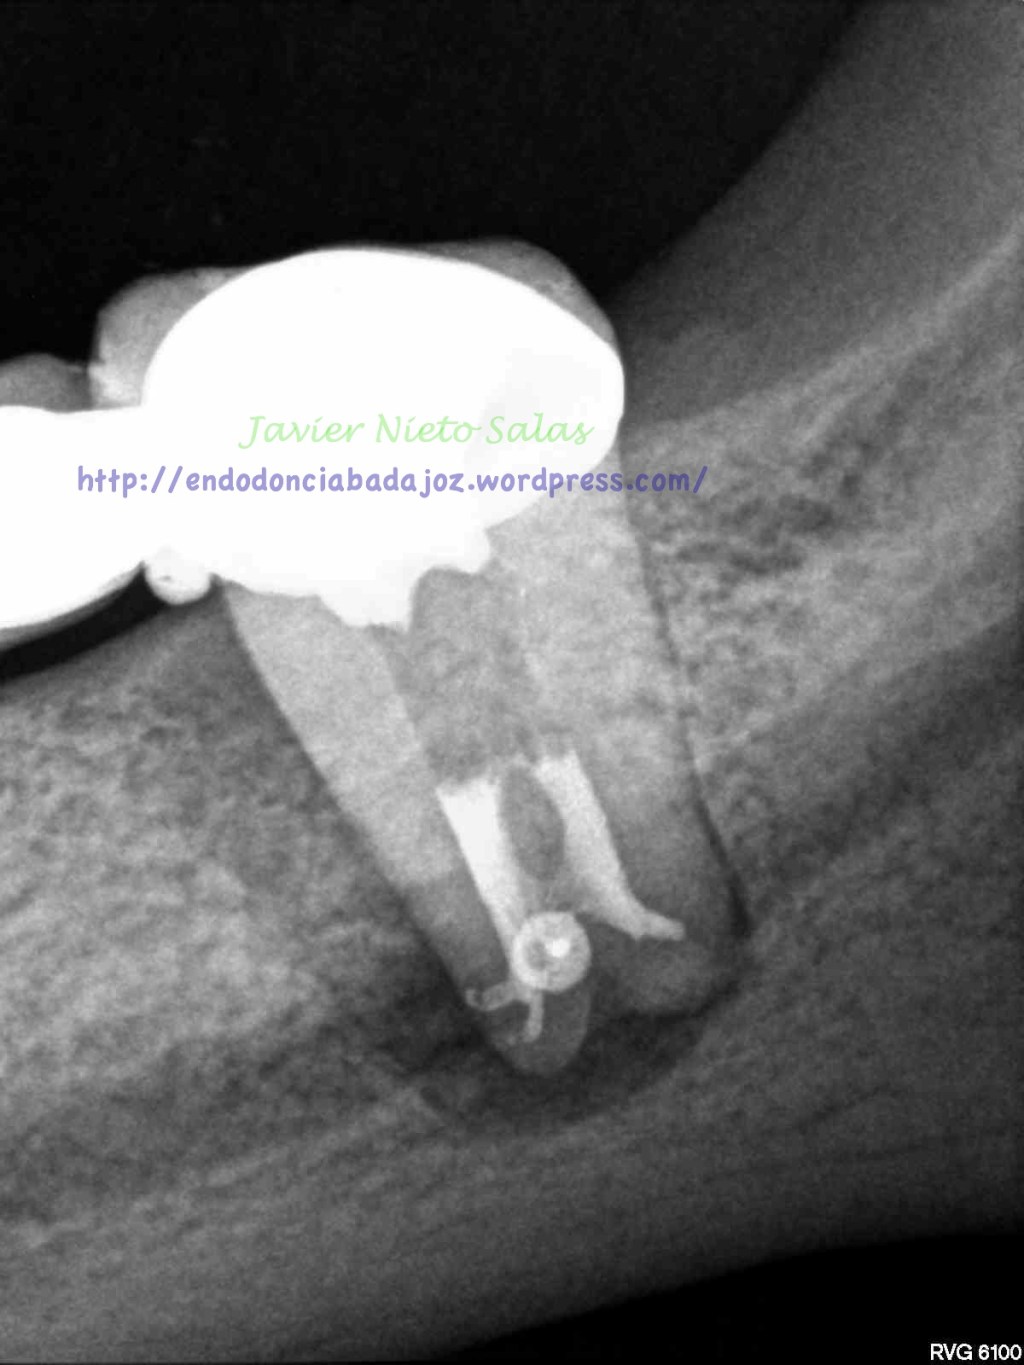

Con lo que, después de tallar los conductos, activar el hipoclorito, pasamos a la obturación, que como hemos adelantado, la realizamos con condensación vertical con la técnica de ola continua de Buchanan, y un backfilling con gutapercha inyectada.

Pero el caso de hoy, no lo cuelgo por su dificultad, lo hago por varios motivos; el primero será el diagnóstico del caso, sólo radiograficamente, en este caso falta información, se puede sospecha de fractura vertical, por varios puntos, se trata de un segundo molar inferior, con un puente desde hace varios años, por la forma de la imagen de la lesión y el sondaje puntual. Pero como es sabido, el problema que tiene una «fractura vertical» es que todos esos signos coinciden con que puede tratarse de un «periodontitis apical crónica», como es el caso.

Pero cual es mi sorpresa y mi tristeza al ver la revisión del caso a los 9 meses. Filtración coronal con gran destrucción de la pieza, muy mal pronóstico.